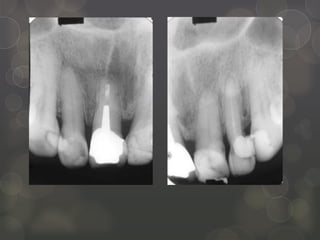

Aumento de coronaclínica  Procedimiento quirúrgico más indicado por odontólogos 1  Reposición apical del margen gingival  Evita que restauración invada el ancho biológico  Estética  Técnicas: Gingivectomía* (< encía adherida) Colgajo de reposicionamiento apical (mantiene cantidad encía adherida) 1 Galagali G, Mahoorkar S. Critical Evaluation of Classification Systems of partially edentulous arches. Int J Dent Clinics. 2010; 3(2): 45-52

http://scielo.isciii.es/scielo.php?pid=S1699-65852011000200002&script=sci_arttext Gingivectomía Incisión horizontal abisel interno (aproximadamente 25o) Realizar 2 incisiones liberadoras más allá de la línea mucogingival, elevando el colgajo y eliminando el rodete de tejido, Remodelado óseo con rotatorios. Reposicionar apicalmente el colgajo, suturar de manera que queda hueso expuesto sólo en interproximal, en estas zonas se coloca cemento quirúrgico